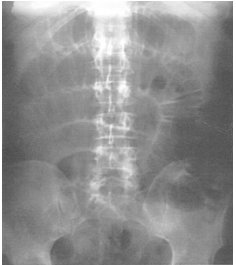

64 李太太今年 56 歲,十年前因為子宮肌瘤接受過子宮切除手術,近幾年來常常肚子悶痛,這兩天吃不 下東西,也吐了兩三次,因此被家屬帶到急診就診,目前體溫 37.8℃,心跳約每分鐘 90 下,血壓量 測為 112/64 mmHg,身體診查發現肚子很脹,目前無明顯 rebounding pain,之後急診醫師幫李太太安 排肚子 X 光和抽血檢查,躺著照的腹部 X 光片如附圖,下列有關李太太的後續治療計劃何者錯誤?

(A)從李太太的病史要高度懷疑 paralytic ileus 的診斷 (B)針對李太太的腹痛和腹脹,放置鼻胃管對症狀解除是有幫助的 (C)要積極給予點滴輸液治療,可以選擇 isotonic saline 或 lactated Ringer solution 以矯正 Na, K, Cl 的不 平衡情形;也要注意病患的尿量狀況,評估輸液治療的反應 (D)另外,要密切注意李太太的肚子疼痛反應,如果腹脹腹痛演變成腹膜炎表現,鼻胃管流出液變得 更像大便顏色,都是需要考慮手術治療的臨床證據